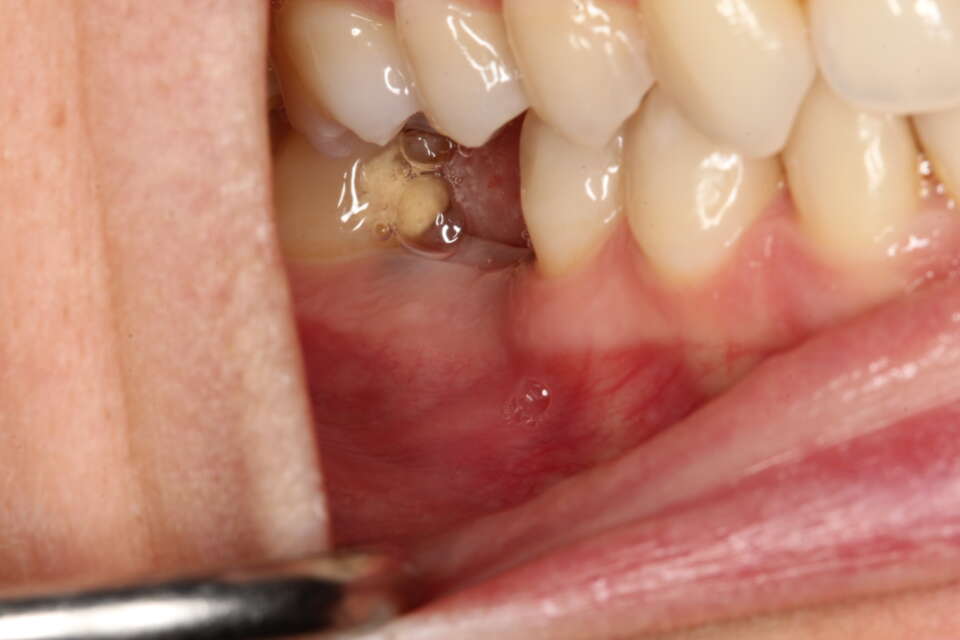

Before Treatment

IMG 6913

IMG 6908

A missing back molar which affects eating and everyday function.